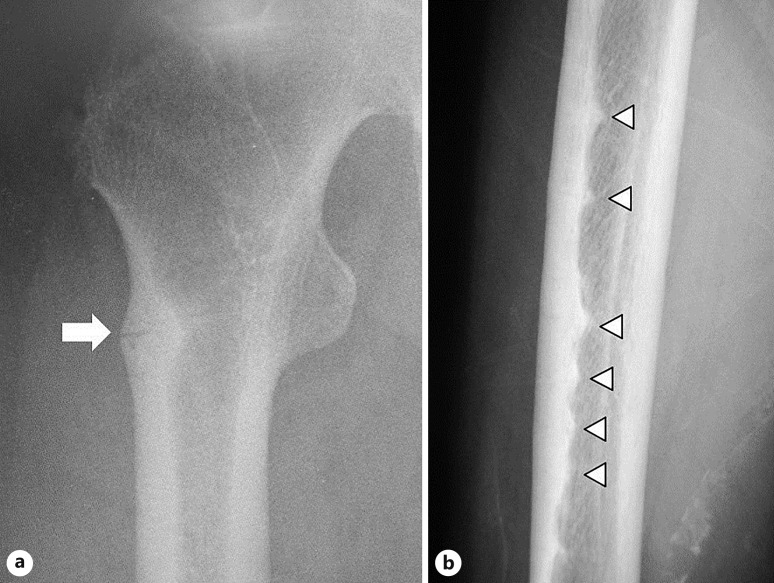

Objectives: Atypical femoral fracture (AFF) is an atypical low-energy subtrochanteric and diaphyseal femoral fracture. Even if bone fusion is achieved in patients with AFF, the risk of AFF in the contralateral femur must be considered. This study aimed to investigate the factors affecting complete AFF in the contralateral femur and conservatively treated incomplete AFF.

Subject and methods: Radiographs of 111 femurs in 104 AFF cases were examined, and the femurs were classified as follows: 85 contralateral femurs with complete AFF; 18 contralateral femurs with incomplete AFF; 8 femurs with incomplete AFF without surgical treatment. Various patients' clinical data were collected, and we investigated the factors affecting the second complete AFF.

Results: Complete fractures occurred in 10 (9.7%) of 103 femurs without incomplete AFF at the first visit and in 3 (37.5%) of 8 femurs with incomplete AFF. The Kaplan-Meier curve revealed that lateral cortical bone thickening and thigh pain were associated with significantly poorer prognoses (p = 0.026 and p = 0.013, respectively). Multivariate analyses revealed that eldecalcitol usage after AFF onset (p = 0.0094) and previous use of bisphosphonate or denosumab (p = 0.0126) were protective factors for second complete AFF and that the presence of thigh pain (p = 0.0134) was a risk factor for second complete AFF.

Conclusions: Eldecalcitol administration after bone union of first AFF may prevent AFF recurrence. In addition, painful incomplete AFF has a high risk of developing a complete fracture.